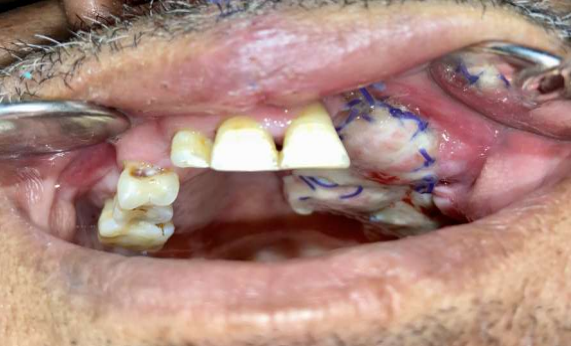

The implants were carefully planned to have abutments aligned with the teeth present in the mandible and to avoid any offset loading as a result of a cantilever. According to literature and also according to the authors experience, the PSI should be kept submerged for at least 6-8 weeks before second stage surgery thus allowing adequate time for healing and stabilisation of the soft tissue component (Figure 8). After waiting for 6 weeks, surgical exposure of the prosthetic components was done, impressions were made with polyvinyl siloxane impression material and the intermaxillary jaw relationship was recorded using aluminum-containing wax (Aluwax; Aluwax Dental Products) (Figure 9,10). The interim prosthesis was delivered and a Porcelain fused to Metal (PFM) permanent prosthesis was planned. A metal try in was done followed by cementation of the final prosthesis (Figure 11). Utilizing high quality porcelain-fused-to-metal, the prosthesis achieved both durability and aesthetic appeal (Figure 12). Gingival porcelain was added to compensate for the lost soft tissue. Occlusal adjustments were made, and speech quality was evaluated. This prosthetic concept achieved patient satisfaction, restored masticatory function, markedly improved speech and improved the lost facial profile contour and lip support.

Figure 9: Exposure of the prosthetic components

Figure 10: Attachment of the abutments

Figure 9

Figure 10